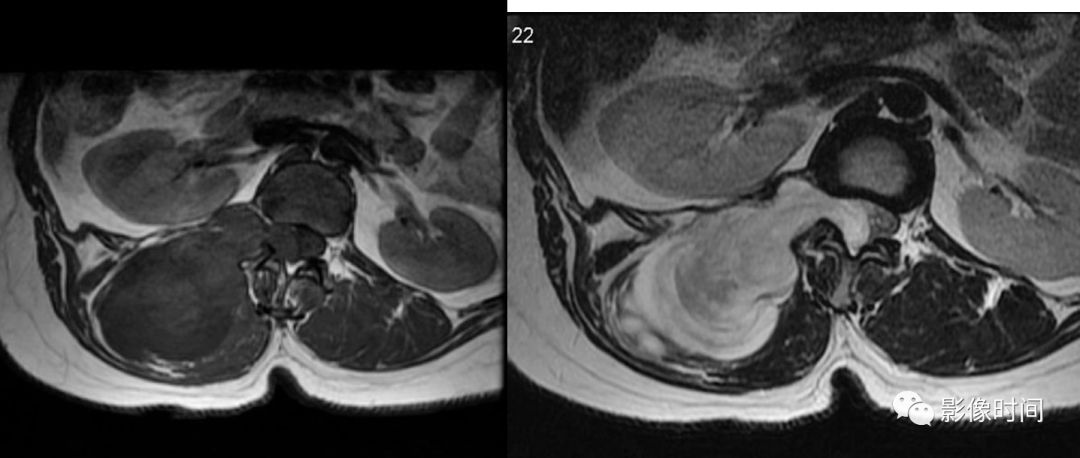

19竹节椎

竹节椎(Bamboo spine)

竹节椎是用于描述强直性脊柱炎的一个放射学特征,由于椎旁韧带广泛骨化,导致椎体融合强直,这种薄而连续的韧带骨化在正位片使得脊柱的轮廓呈现波浪起伏状,宛如具有多个竹节的一根竹竿,故而得名。

典型病例

强直性脊柱炎。腰椎正位片示腰椎韧带、小关节囊广泛骨化,骨性强直,呈典型竹节椎表现。另可见骶髂关节骨性融合。